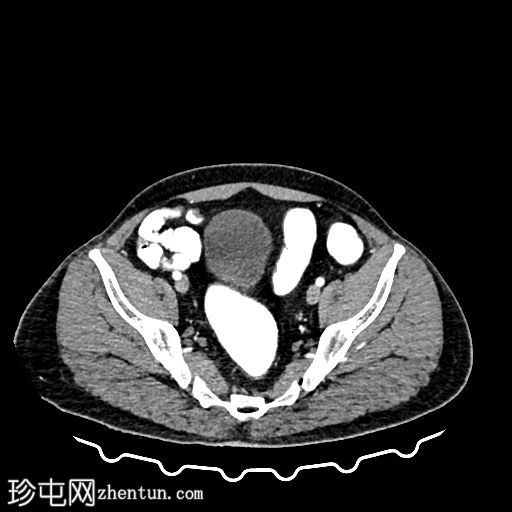

CT

轴位

平扫

轴位增强扫描

动脉期

门静脉期

冠状位增强扫描

乙状结肠旁可见两处小的脂肪衰减病灶。较小的病灶呈周边环状强化,伴有轻度邻近脂肪条索状改变 → 急性大网膜垂炎。

较大的病灶呈薄环状强化,周围无炎症 → 消退期/慢

性病

变。未见肠壁增厚,未见肠腔相通,无游离液体或积液。